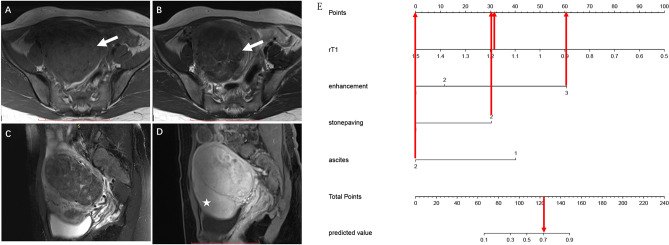

A nomogram was constructed based on the multivariate logistic regression results of Model 3 (Fig. 3A). The calibration curve (Fig. 3B) of the nomogram showed that the calibration between the predicted and actual outcomes of tumor identification was good. DCA analysis showed that the nomogram was clinically useful, with a high net benefit over a wide range of threshold levels (Fig. 3C). Figure 4 shows a representative case of the OF group, whereas Fig. 5 shows a representative case of the BLM group.

Figure 5.

A 43-year-old woman with a BLM. (A) Axial T1-weighted imaging shows a hypointense tumor in the right adnexal region. (B) On T2-weighted imaging, the tumor exhibits a stone paving sign (white arrow). (C) None pelvic effusion was found in the pelvic. (D) The tumor shows avid contrast enhancement (white arrow) comparing with the uterus (asterisk). (E) This tumor’s total score is 124 (r-T1 = 32, enhancement = 61, stone paving = 31, ascites = 0) with a predicted value of 0.71 calculated by the nomogram; the corresponding probability of BLM is 71%.